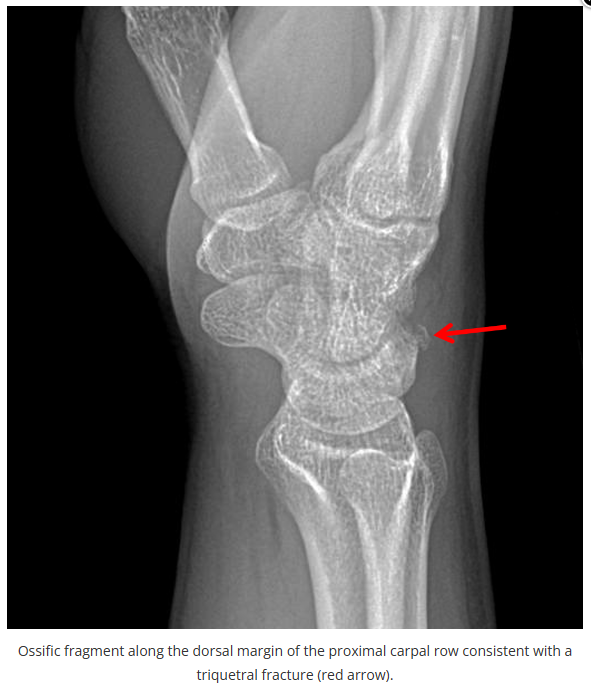

X线读片是骨科医生的基本功。

今天是腕部与手的X线片。所有X线片都

带有标注和说明

,可以选择长按图片,

自动翻译相关说明

进阶篇